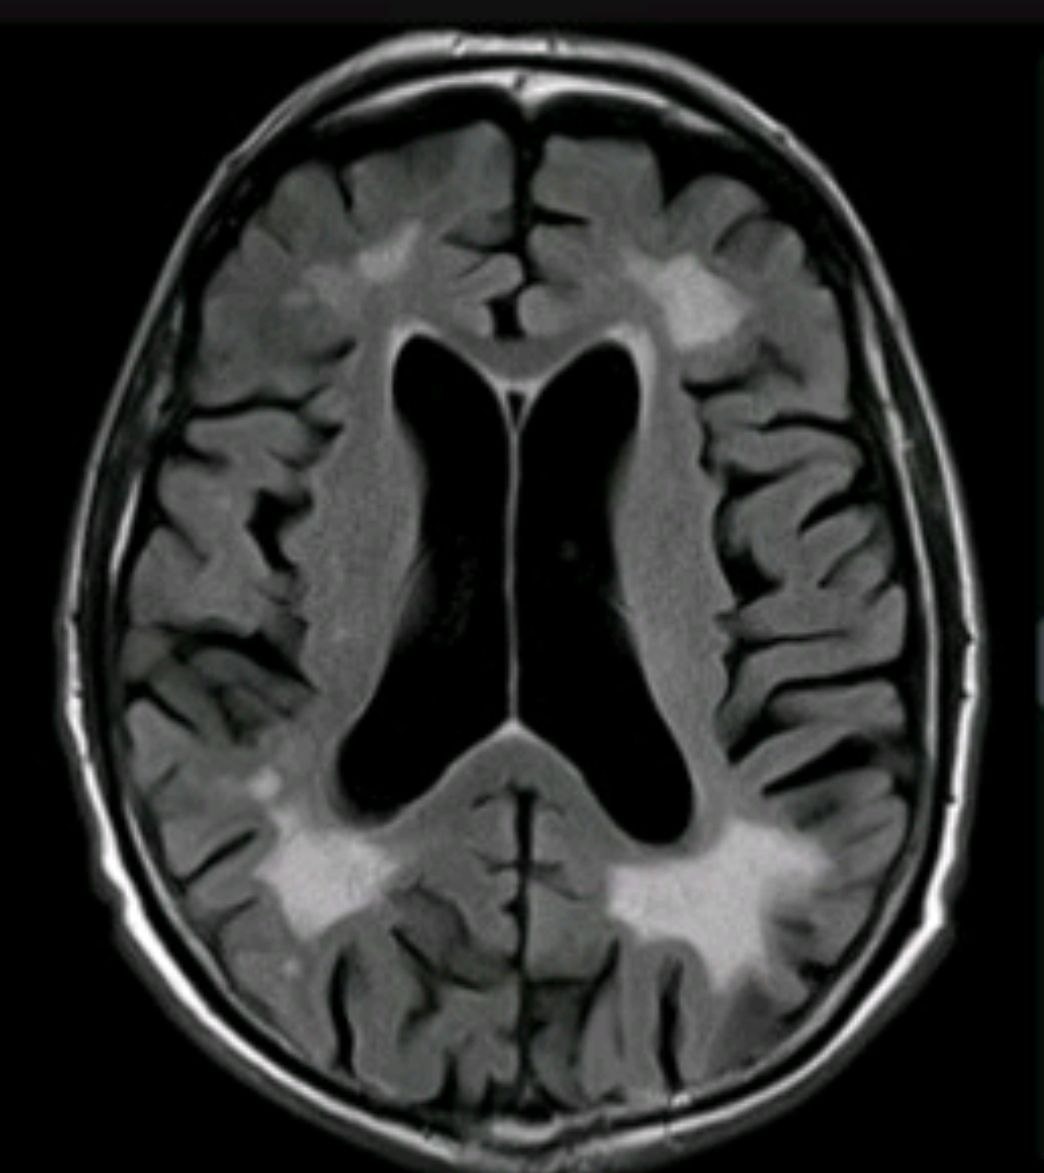

Хроническая ишемия головного мозга на МРТ.

🧠 Хроническая ишемия головного мозга — это состояние, при котором ткань головного мозга не получает достаточного количества кислорода и питательных веществ из-за недостаточного кровоснабжения. Это может произойти в результате различных факторов, основными из которых являются атеросклероз, артериальная гипертензия, диабет.

➡️ В результате в веществе головного мозга происходит постепенное замещение нормальной мозговой ткани клетками глии - появляются очаги и фокусы глиоза.

👀 По МРТ в первую очередь мы оцениваем эти изменения на T2 ВИ и импульсной последовательности FLAIR, на которых очаги глиоза имеют гиперинтенсивный МР-сигнал, по Т1 ВИ данные очаги могут быть изо-гипоинтенсивны.

Данные очаги зачастую сливаются в зоны глиоза, на фоне которых мы нередко видим лакунарные кисты - последствия лакунарных инсультов.